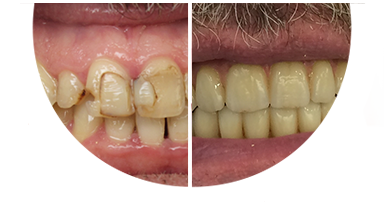

Paciente de 76 anos do sexo masculino

Motivo da consulta: Paciente desdentado total, procurava colocar dentes.

Plano de tratamento: Colocação de 4 implantes superiores e 2 implantes inferiores. Confeção de uma barra superior e colocação de 2 locators® na parte inferior. Confeção de uma prótese superior e outra inferior removível, com encaixes na barra e locators®.

A escolha deste plano de tratamento deve-se ao facto de o paciente querer uma solução total, mas não completamente fixa, uma vez que não tinha muita destreza manual para higienizar uma prótese fixa. Desta forma, conseguiu uma solução bastante retentiva (devido aos encaixes) mas que consegue remover para uma higienização correta.